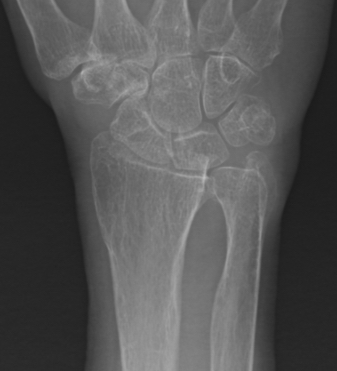

Distal radius fracture with DRUJ instability

Management

DRUJ instability after distal radius fracture ORIF

- 100 cases of DRUJ instability after distal radius ORIF

- 50 treated with arthroscopic capsular repair

- 50 treated in cast

- better outcomes with capsular repair

www.boneschool.com/distal-radius-fractures